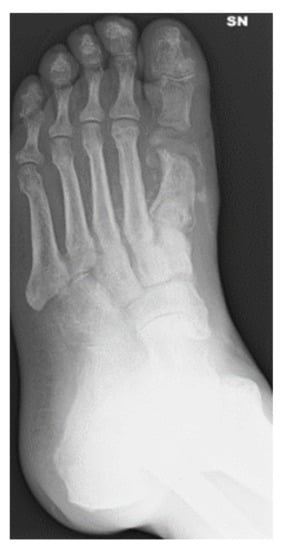

3.2. Metatarsal Lesions